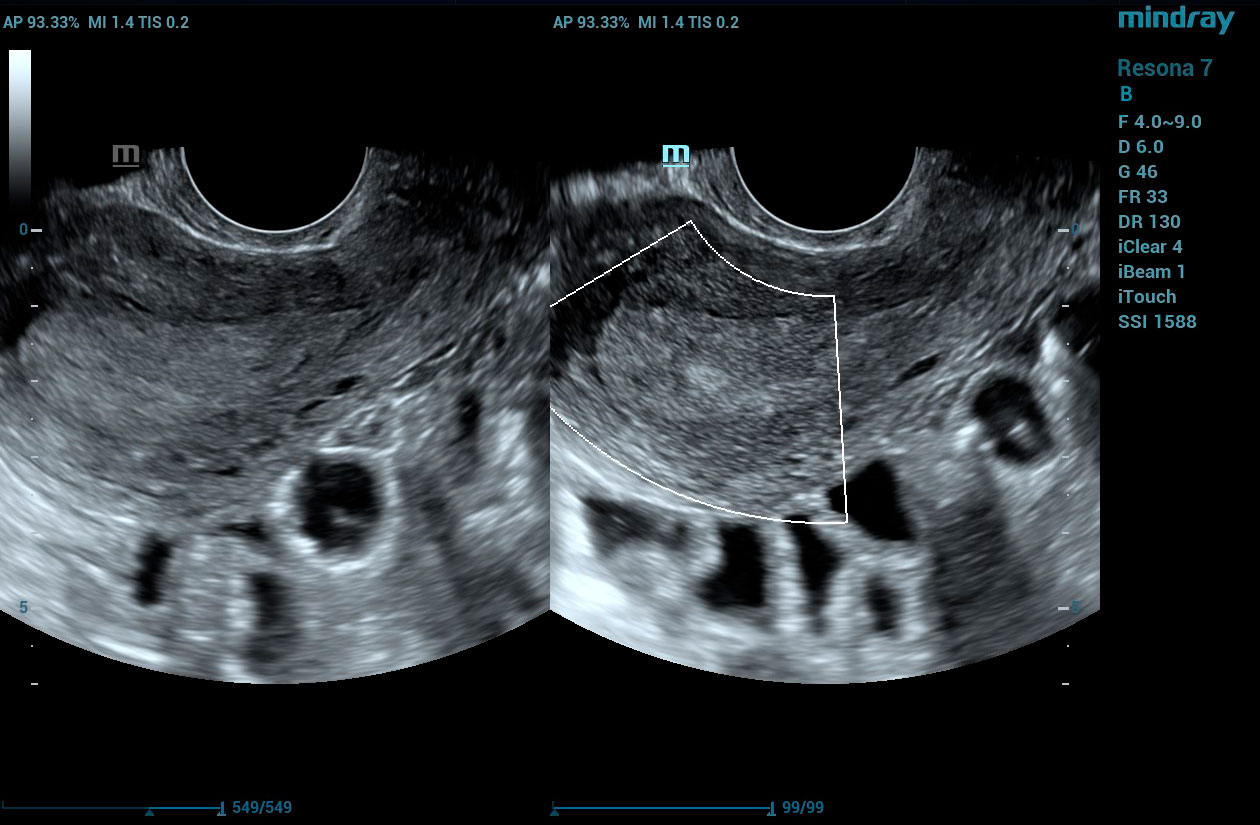

HD Scope

HD Scope is an advanced B-mode image processing technique that focuses additional imaging resources within a specified region of interest (ROI), analyzes the received channel data in unique ways, and applies various filtering and processing algorithms. This results in enhanced contrast resolution within the ROI based on the acoustic characteristics of varying tissue types.